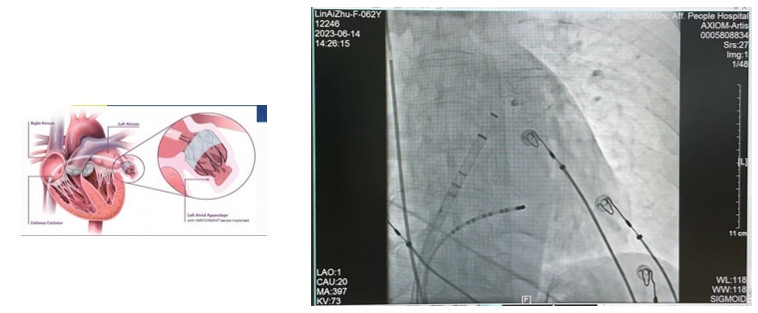

左心耳封堵術(shù)